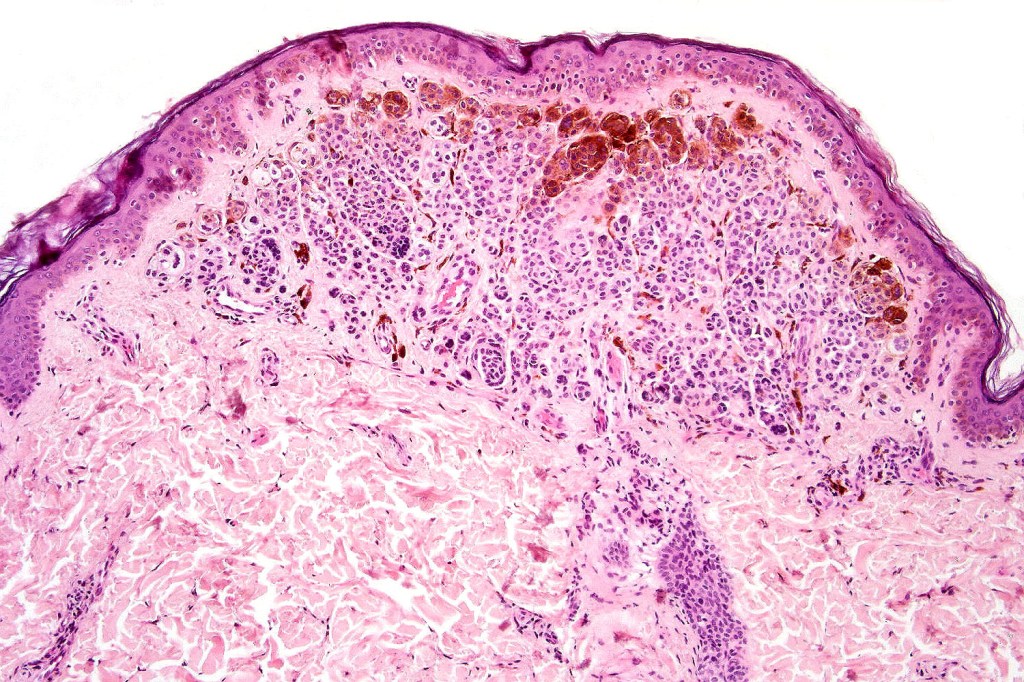

.Balloon cell change is most often seen in banal melanocytic nevi but it has also rarely been described in cellular blue nevus, dysplastic nevus, combined nevus, halo nevus & Spitz nevus. Lesions with <50% of balloon cells are sometimes described as nevi with balloon cells. Nevi with >50% balloon cells are described as balloon cell nevus.

.Balloon cell nevs genrally has uniform, hyperchromatic nuceli (as opposed to the vesicular nuclei with prominent nucleoli) seen in melanoma. Mitoses are absent.(In my experience, balloon cell melanoma is more common than balloon cell nevus).

The importance of the entity is that it must always be distinguished from balloon cell melanoma. All cases should be scrutinized very carefully for pleomorphism and mitotic activiy before rendering a diagnosis of balloon cell nevus.